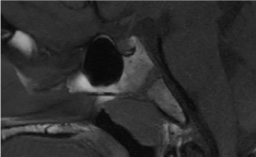

IRM de l’hypophyse normale ou presque : artefacts, kystes de la poche de Rathke – Claire Ancelet

Ce syndrome rare est caractérisé par une hypophyse postérieure absente ou ectopique, une tige interrompue et une hypoplasie hypophysaire antérieure…